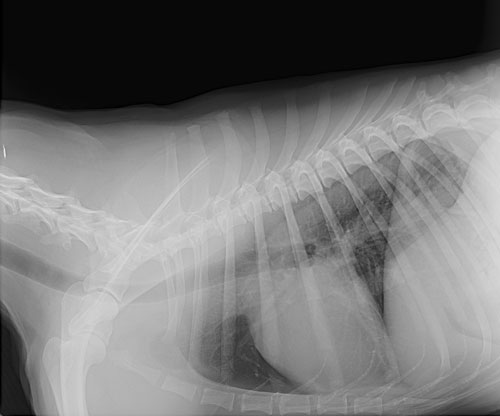

Radiographs can be used to diagnose fractured bones, intestinal foreign bodies, bladder stones, and can be a useful tool in cardiac disease.